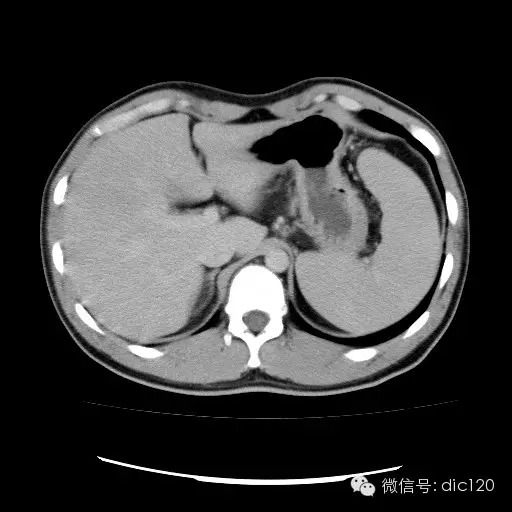

| 影像表现及分析: | 影像表现:动脉期扫描肝右叶紧贴边缘见一过性楔形高密度强化区,边界清,边缘平直,临近血管走形自然,门静脉期期恢复正常肝实质密度,延迟保持与肝实质密度一致。 |

1、FNH:动脉期明显强化,门脉期一般为略高或等密度;若中心呈放射状分布的纤维瘢痕组织是特征性改变。 2、肝腺瘤:与长期口服避孕药有关,动脉期可见早期强化,强化程度高,持续时间长,静脉期为低密度,可见包膜或肿瘤内出血。 3、肝细胞肝癌:动脉期扫描时病灶明显强化,而门脉期和延迟期扫描时病灶密度下降,呈“快进快出”特点。肝细胞肝癌患者多有肝炎,肝硬化病史,可伴有AFP升高; 肝血管瘤:典型肝血管瘤为边界清楚密度均匀的低密度影,增强扫描动脉期周边首先强化,呈结节状或环状,强化较明显,静脉期及延迟期并向内扩散。 |

| 疾病总结: | 正常肝脏的双重血供并非2个独立系统,两者之间有许多交通吻合,包括①肝窦间通路.②脉管间途径.③血管丛途径,即胆管周围血管丛途径.当肝脏发生血供障碍时,通过神经一体液因素的调节这些交通吻合支开放,双重供血发生血流量的变化甚至血流方向的改变.肝脏的这种”一过性”灌注异常在SCT表现为肝动脉期一过性肝实质强化(THPE).一过性肝实质强化差异是SCT增强扫描于肝动脉期表现的肝脏一过性灌注异常,大多数情况下它反映了局部肝脏双重血供的重新分布,即局部肝实质门静脉或肝静脉血流量减少,肝动脉血流量增多或为肝动脉门静脉分流或局部肝脏的变异或迷走血供所致。典型CT表现为肝动脉期一过性楔形或三角形高密度强化区,边缘平直,常位于肝脏边缘部位,其中血管走行正常,门静脉期恢复为正常肝实质密度。放射学医师应加强对一过性肝实质强化CT表现的认识。 |